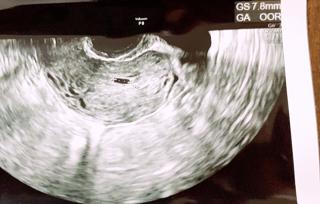

年明けから何となく熱っぽさが続いていて、検査薬を試したらすぐに陽性反応が! 予約を取って病院で診て貰うと、妊娠5週目との事。 胎嚢は7.8mmと平均より小さいとの事。このまま育たない可能性もあるかもしれないと言われたけど、まだ初診ですからね。2回目以降の診察で言われるならまだしも... 小さくてもちゃんと生きてます。 次回の健診が楽しみです。